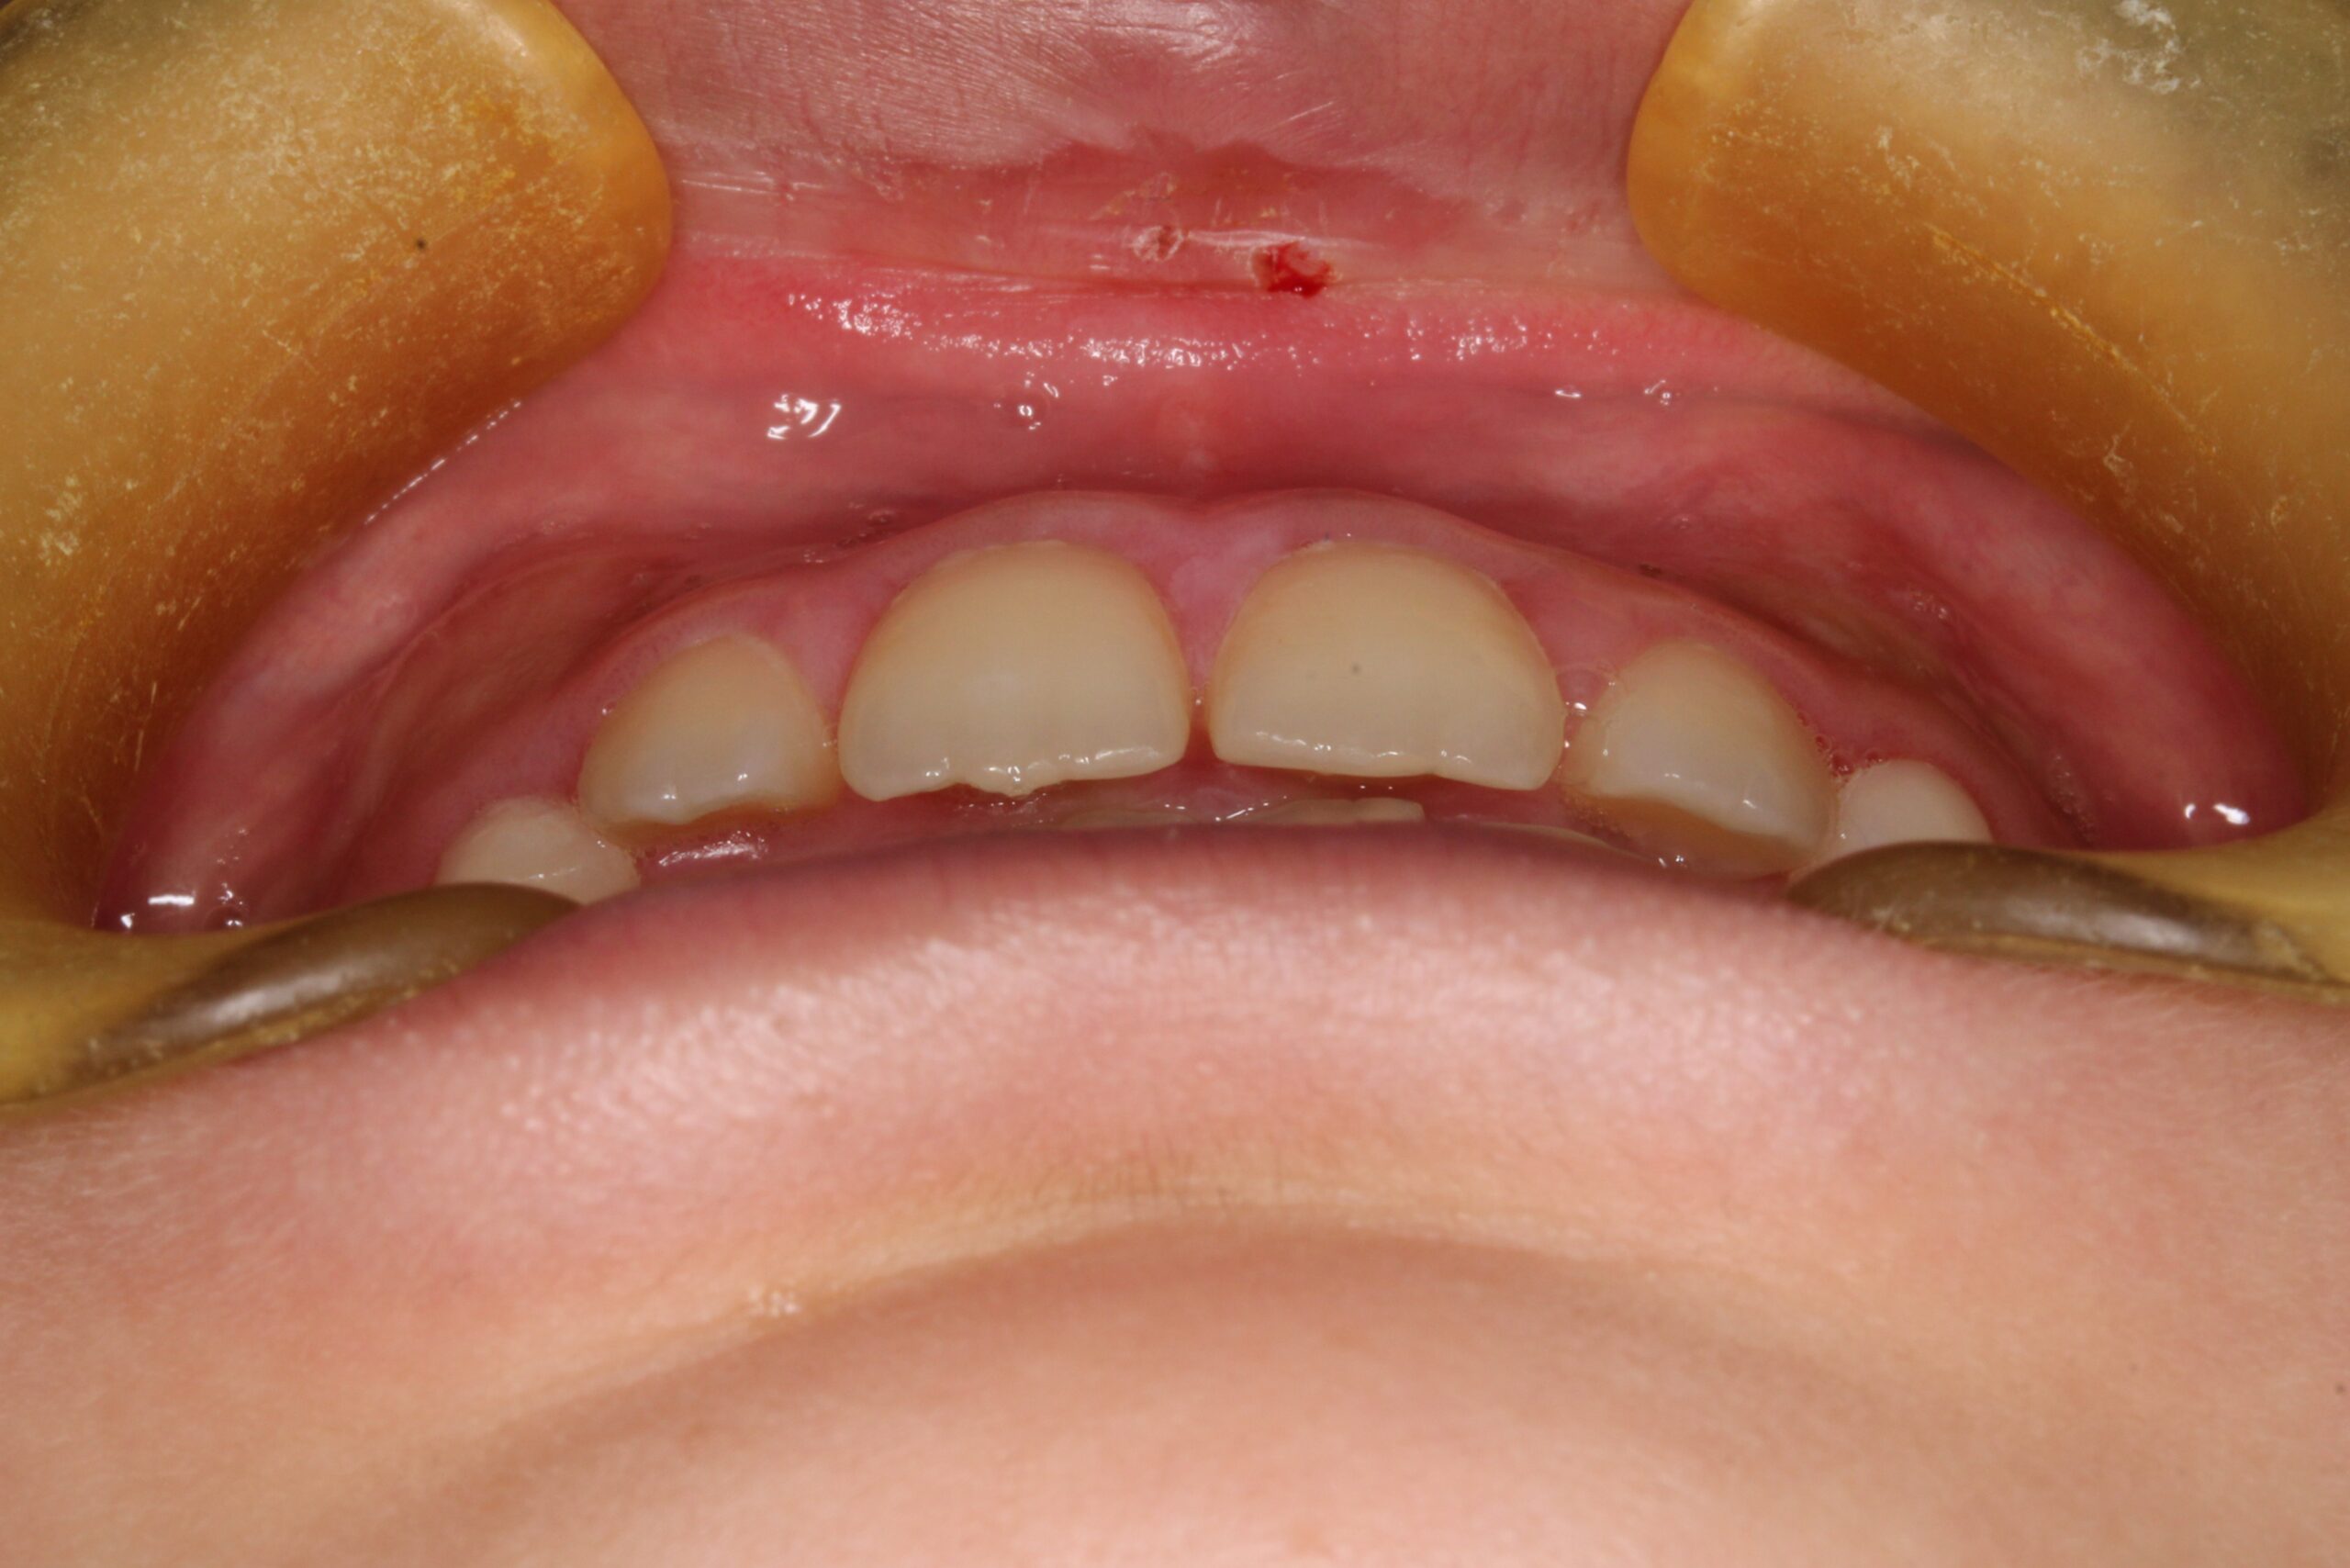

矯正術前:正面

矯正術後:正面